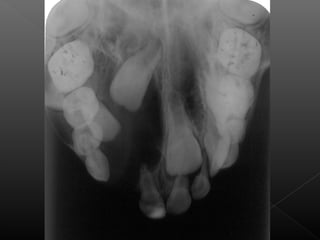

Este documento describe las radiografías oclusales y panorámicas, incluyendo sus usos y técnicas. Las radiografías oclusales se utilizan para examinar grandes áreas de los maxilares y se colocan entre las superficies oclusales cuando el paciente muerde suavemente. Las panorámicas permiten ver los maxilares y la mandíbula en una sola imagen. El documento también explica diferentes tipos de radiografías periapicales y sus ángulos de inclinación.